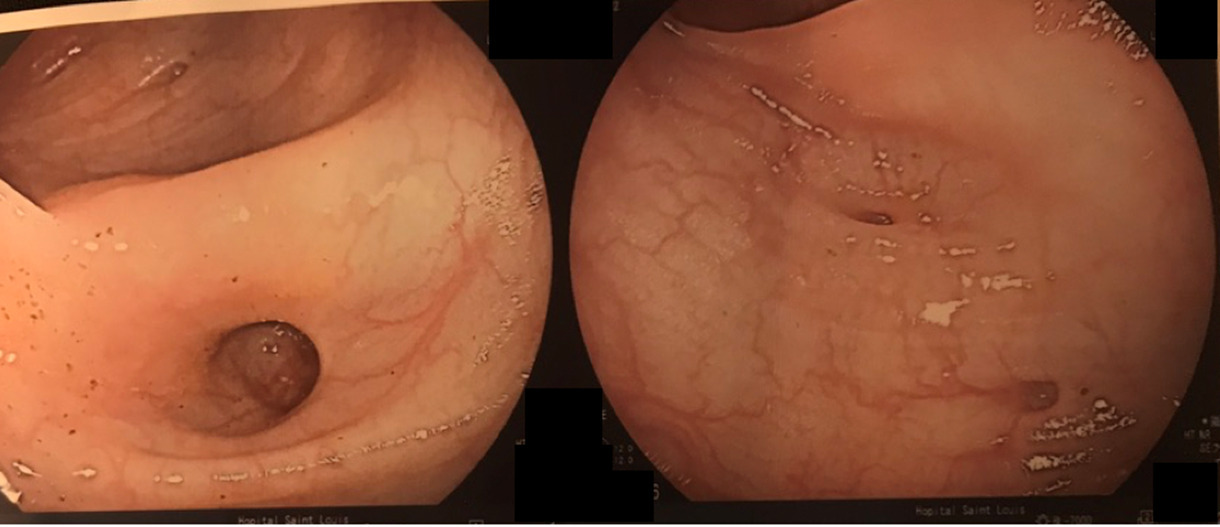

Les hémorroïdes peuvent se manifester de plusieurs façons : par des saignements, par une sensation de boule/gêne au niveau de l’anus et par des douleurs anales à type de cuisson.

Un prolapsus rectal est une extériorisation de la muqueuse rectale à travers l’anus. Il peut entraîner une sensation de gêne au niveau de l’anus de façon intermittente ainsi que des saignements et une incontinence anale.